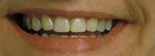

Före behandling av utrymmesanomali (trångställning) Efter behandling av utrymmesanomali (trångställning)

Före behandling av utrymmesanomali (glesställning) Efter behandling av utrymmesanomali (glesställning)

Före behandling av utrymmesanomali (trångställning och överbett) Efter behandling av utrymmesanomali (trångställning och överbett)

Utrymmesproblem beror på att det antingen saknas tänder, eller att det finns för många, alternativt att käkarna är för små eller för stora. Tänder kan vara trångställda, beroende på att det är ont om plats i käkbenet. Det omvända problemet finns också, det vill säga att tänderna är glesställda så ett mellanrum bildas.